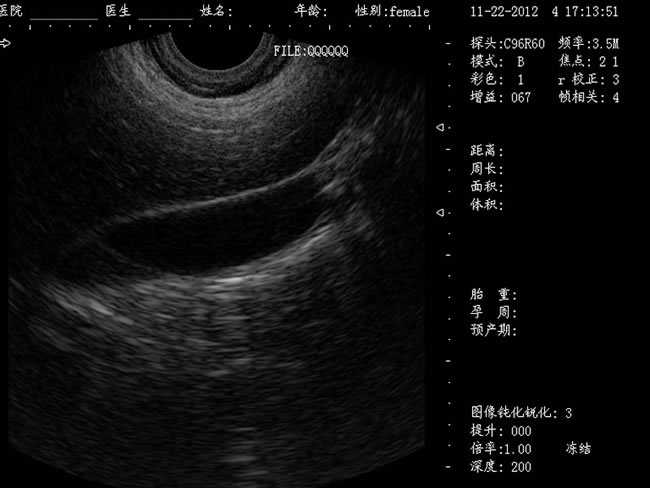

DW-460

功能特點:

婦產科手術監視儀-可視人流機掃描角度:

a) 6.5MHz腔內探頭:152º可視可調;

b) 3.5MHz凸陣探頭:60º可視可調;

TGC 調節:總增益、8 段TGC 調節器。

圖像放大:實時放大(16 級可調),局部放大(≥2 倍)。

圖像調節:黑白、左右、上下、亮度、對比度、焦點數、焦點間距、焦點位置、動態范圍、掃描角度、掃描線密度、聲功率、幀相關、M 速度。

圖像處理:圖像平滑/銳化、組織諧波、伽瑪校正、直方圖。

注釋功能:日期,時鐘,姓名,病歷號,性別,年齡,醫生、醫院、全屏幕字符編輯。

體位標記:≥30 種。